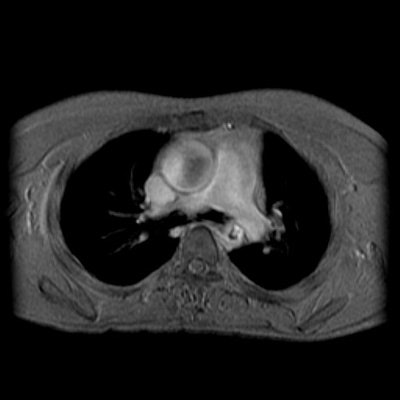

Flow images reveal signal void in the descending aorta at the level of stenosis consistent with turbulent flow. Some signal void is also noted in the ascending aorta- likely related to the bicuspid valve.